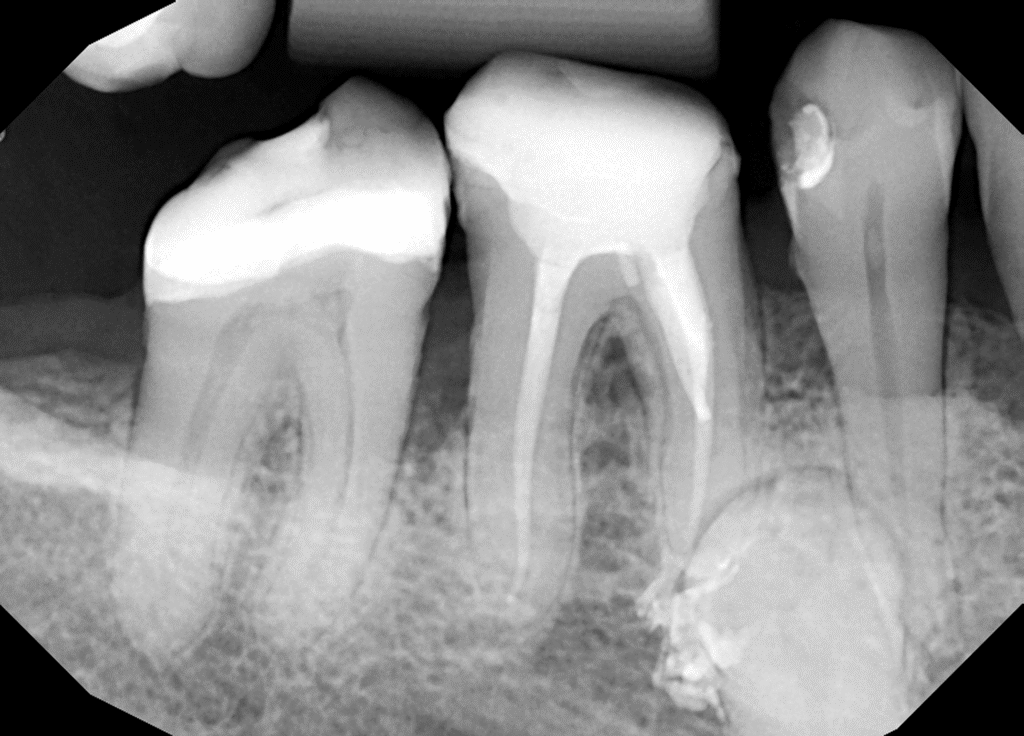

Pacjentka lat 54 trafiła do mojej kliniki skierowana z innego gabinetu celem leczenia endodontycznego zęba 46. W badaniu stwierdziłem znaczny zanik światła kanału korzeniowego. W badaniu tomograficznym stwierdziłem całkowity zanik kanału korzeniowego w strefie mezjalnej. Korzeń dystalny mimo widocznego światła kanału na CBCT, widoczne było wiele zwapnień w środkowej części kanału. Po wykonaniu dostępu endodontycznego zlokalizowałem materiał wypełniający kanał pozostawiony po poprzednim nieskutecznym leczeniu endodontycznym. Do usunięcia wykorzystałem laser 2780nm (25mJ/puls). W kolejnych etapach instrumentacji wspomaganie ultradźwiękami oczyściłem strefy mezjalną i dystalną. Instrumentacja themo-

mechaniczna polegała na zastosowaniu protokołu ciągłej chelacji wraz z użyciem lasera

2780nm z końcówką płaską (50mJ/puls) celem udrożnienia przestrzeni endodontycznych. Po wstępnym uzyskaniu drożności zastosowałem instrumentację maszynową wspomagająco celem udrożnienia przestrzeni. Finalnie obturacja z zastosowaniem ćwieków gutaperkowych kalibrowanych na WL i uszczelniacza na bazie krzemianów wapnia. W przeciwieństwie do tradycyjnych uszczelniaczy, nie wymaga mieszania, co eliminuje błędy w proporcjach i zapewnia powtarzalną konsystencję. Jest materiałem wysoce biokompatybilnym i bioaktywnym. Finalnie zamknięto ząb odbudową kompozytową tymczasową i skierowano na dalsze leczenie protetyczne do gabinetu kierującego pacjenta.